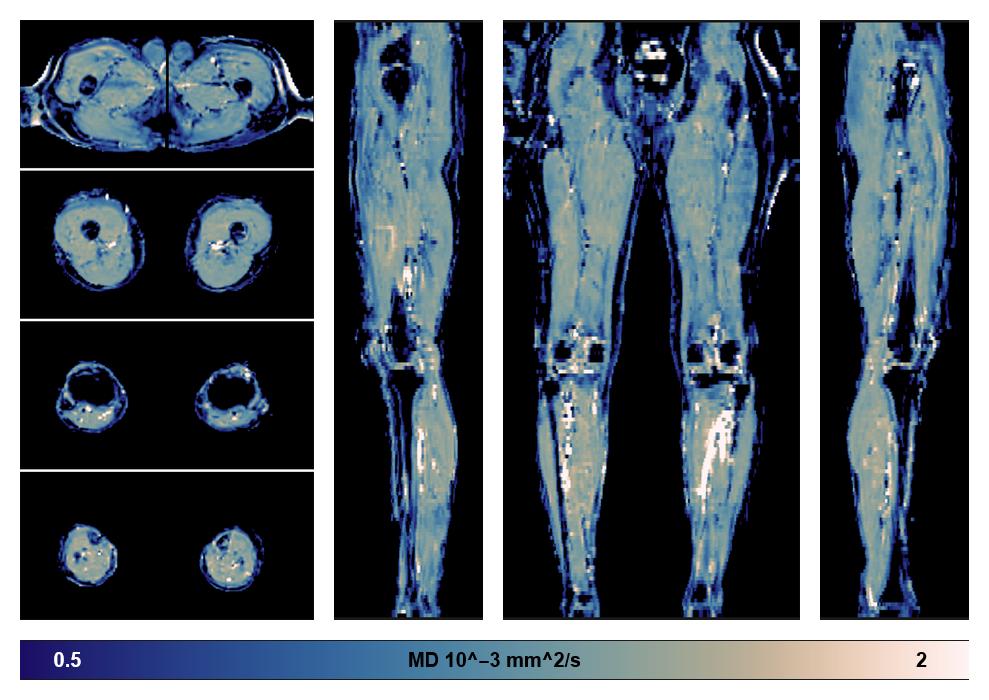

• Mean diffusivity

IVIM corrected whole leg muscle mean diffusivity obtained from diffusion tensor imaging.